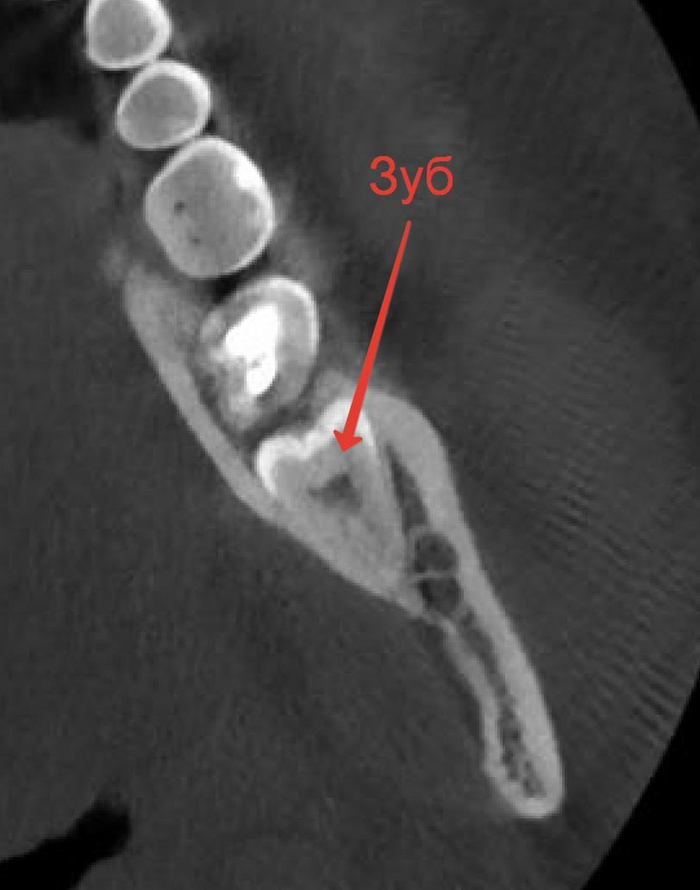

Вот пациент! Мужчина, 33 года. Смотрим на компьютерную томографию. Левая нижняя восьмерка, полностью в кости, вид сбоку. Удаляется по причине сдвигания нижнего зубного ряда.

Теперь вид в разрезе, то есть ради чего и делалась эта томография. Тут мы увидим детальнее расположение нижнего альвеолярного нерва, который многие путают с лицевым. Этот нерв располагается вплотную к корню и если его повредить, то у пациента возникнет онемение нижней губы и подбородка с одной стороны.